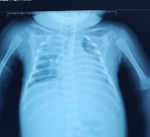

Diagnostic assessment: the cerebral computed tomography (CT) scan (Figure 1) showed the presence at the level of tubular hyperdensity subarachnoid well-limited spaces, realizing the "cord sign" harmonious with a thrombus of the cortical veins, associated with bilateral hypodense foci with a hemorrhagic component. The set of these lesions was associated with edematous infiltration of soft tissues of the left parietal scalp related to a hematoma in the process of liquefaction. The chest X-ray (Figure 2) demonstrated a bilateral alveolo-interstitial syndrome. The complete blood count showed a microcytic hypochromic anemia at 4.9g/l, a leucopenia at 3,900/ul; a neutropenia at 1000, a lymphopenia at 1000, and thrombocytopenia at 107.000/ul. The CRP at 116 mg/l, a TP at 23%, TCK: 43 sec, ALT 779 IU/L, AST 500 IU/L, albuminemia: 27 g/L, urea 7.52 mmol/L, and creatinine: 31.82 ùmol/L. The hemoculture remained sterile, whereas the cytobacteriological study of sputum isolated a Klebsiella pneumoniae. Facing the seriousness of the clinical picture associated with the pancytopenia, the persistent lymphopenia, and the hepatocellular insufficiency, a rapid HIV test was positive. The viral load was 2,760,000 copies/ml, confirming the infection by the human immunodeficiency virus.

Figure 1: front chest X-ray in a supine position, demonstrating a systematized alveolar location of the right upper lobe associated with a scattered bilateral interstitial syndrome